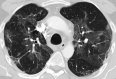

The potential mid-term and long-term consequences after severe acute respiratory syndrome coronavirus 2 (SARS-CoV-2) infections are as yet unknown. This is the first report of bronchoscopically verified organizing pneumonia as a complication of coronavirus disease 2019 (Covid19). It caused persisting dyspnea, impaired pulmonary function, and radiological abnormalities over 5 weeks after onset of symptoms. While organizing pneumonia frequently requires treatment with systemic corticosteroids, in this case it resolved spontaneously without treatment after 6 weeks. Healthcare professionals should consider organizing pneumonia in patients with persisting respiratory symptoms after Covid19.